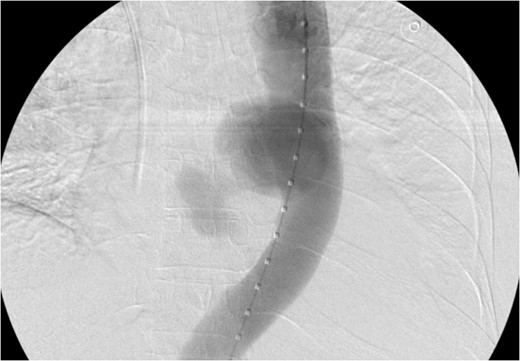

Aortogram showing successful deployment of covered stent graft.

TEVAR can be safely employed to treat an aorto-esophageal mycotic thoracic aneurysm when open repair is not possible because of patient’s comorbidity. Post-operatively our patient was asymptomatic and imaging demonstrated the stent graft in excellent position, without endoleak, and complete resolution of the aneurysm sac. Long-term follow-up is necessary for detection of endoleak, recurrence, or aneurysm propagation.